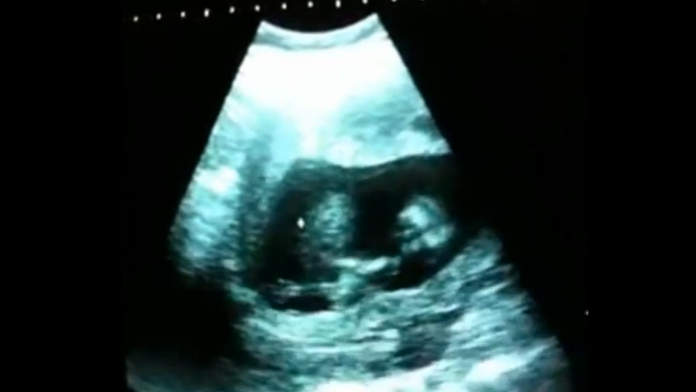

To, čo v tehotenskom brušku vystrája táto nezbednica vás zaručene pobaví.

Každá žena by mala počas tehotenstva absolvovať ultrazvulk, aby sa vedelo, či je s plodom všetko v poriadku. Tak urobil aj tento šťastný pár. Nečakali však, že ich vytúžené dievčatko je až takáto huncútka. A ešte aj s talentom!

Hoci niektoré bábätká v brušku vedia narobiť tiakisto veľkú šou, toto dievčatko sa vie zabávať skutočne jedinečným spôsobom. Údajne to svedčí o tom, že je šťastná a zdravá. Video pripravil portál Dobré noviny a za krátky čas sa stihlo stať hitom internetu. Pozrite si jej šantenie aj vy.